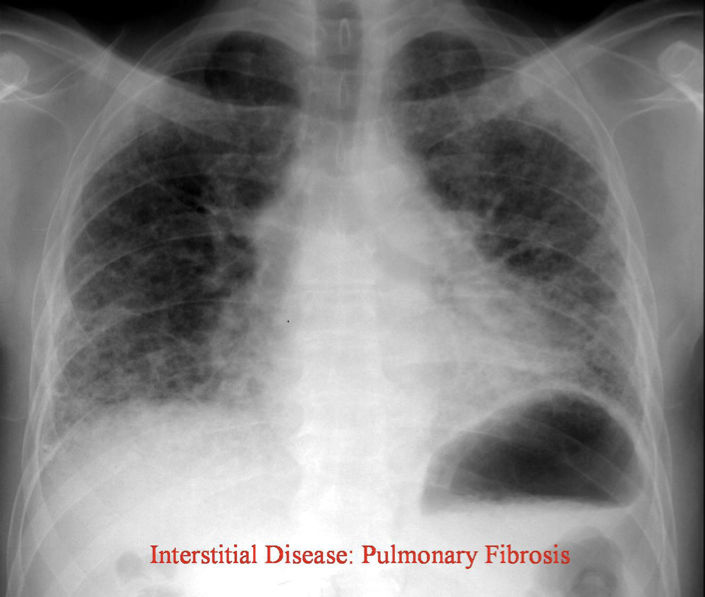

How would you describe the interstitial pattern on CXR in pulmonary fibrosis?

Reticulonodular